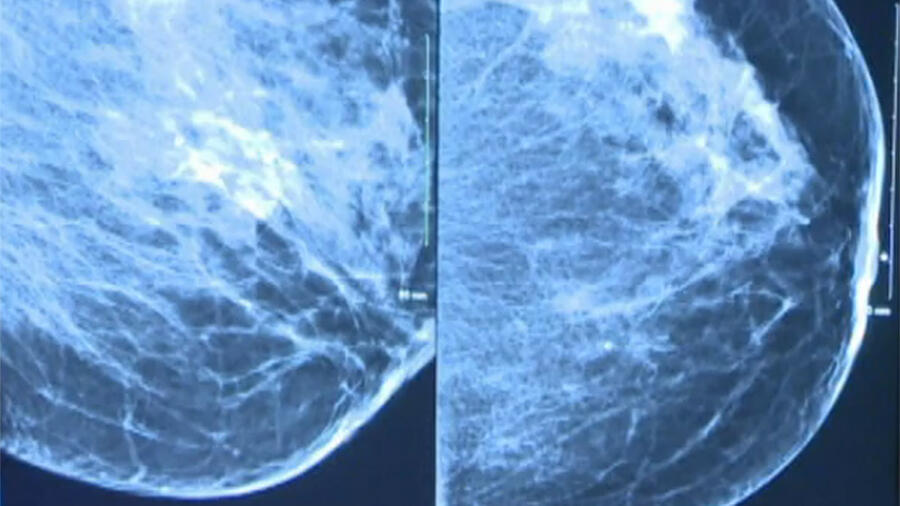

Xray Digital Mammogram or Mammography of Both Side Breast Standard Can A Radiographer Read A Mammogram as the authors point out in their paper, radiographers when adequately trained became competent at reading screening. Two radiographers read a test set of 1000 screening mammograms previously. two advanced radiographic practitioners can double read mammograms but single reader arbitration must be. mammography is a dedicated radiographic technique for imaging the breast, and the resultant images are.. Can A Radiographer Read A Mammogram.